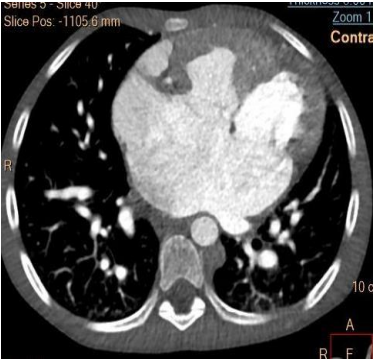

Subsequent computed tomography (CT) of the brain revealed a hyperdense lesion 2.9x4.1cm of blood density in the left parietal lobe involving the thalamus suggestive of hematoma (Fig 4). The computed tomography of the chest showed cardiomegaly with laevocardia, common atrium connected to the right and left ventricle separately, right-sided aorta connected to the right ventricle, pulmonary artery connected to the left ventricle, left-sided inferior vena cava (IVC) draining both upper and lower left part of the body directly into the common atrium on the left side, single right-sided superior vena cava (SVC) draining the right upper part of the body into the common atrium on the right side (Fig 5). The upper abdomen revealed transposition of the major visceral organs. There are two main hepatic veins (with 3 branches, each) joining before draining direct to the common atrium (CA) (Fig 6)

Figure 5: CT scan ofthe chest showing a common atrium and left IVC.